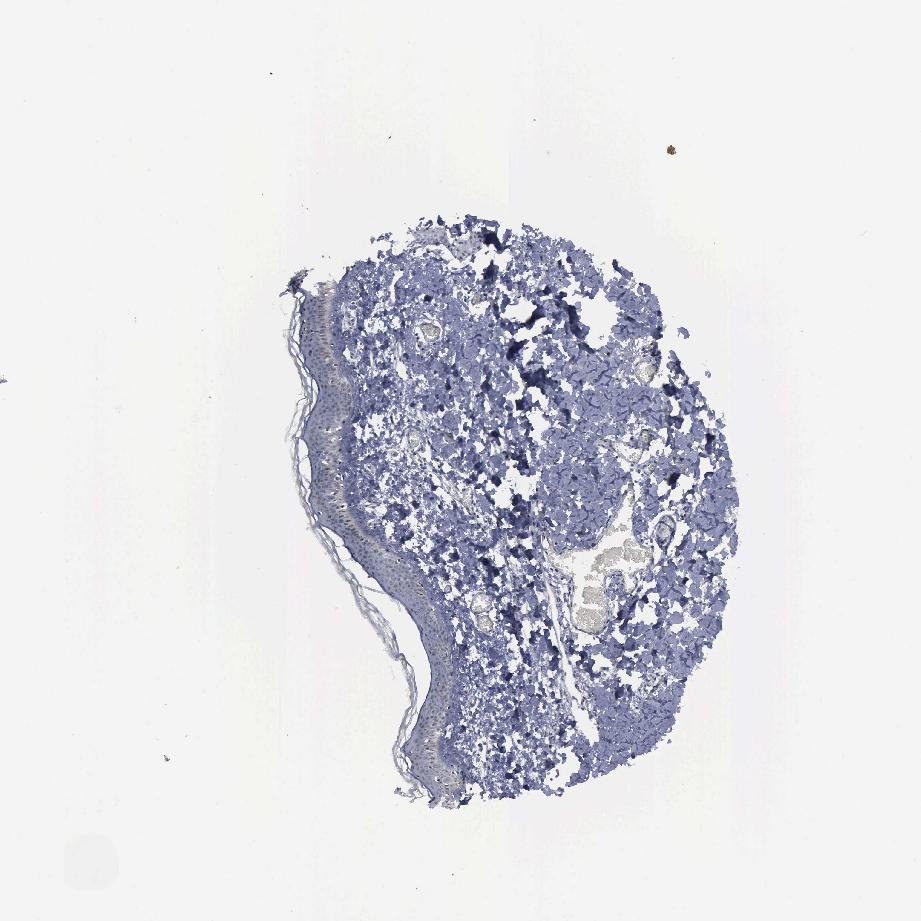

SKIN 2 - Antibody stainingi

Antibody staining in the annotated cell types in the current human tissue is reported as not detected, low, medium, or high, based on conventional immunohistochemistry profiling in selected tissues. This score is based on the combination of the staining intensity and fraction of stained cells.

Each image is clickable and will lead to virtual microscopy that enables deeper exploration of all samples and also displays staining intensity scores, fraction scores and subcellular localization as well as patient and tissue information for each sample.

Antibody HPA001063

Epidermal cells Not detected